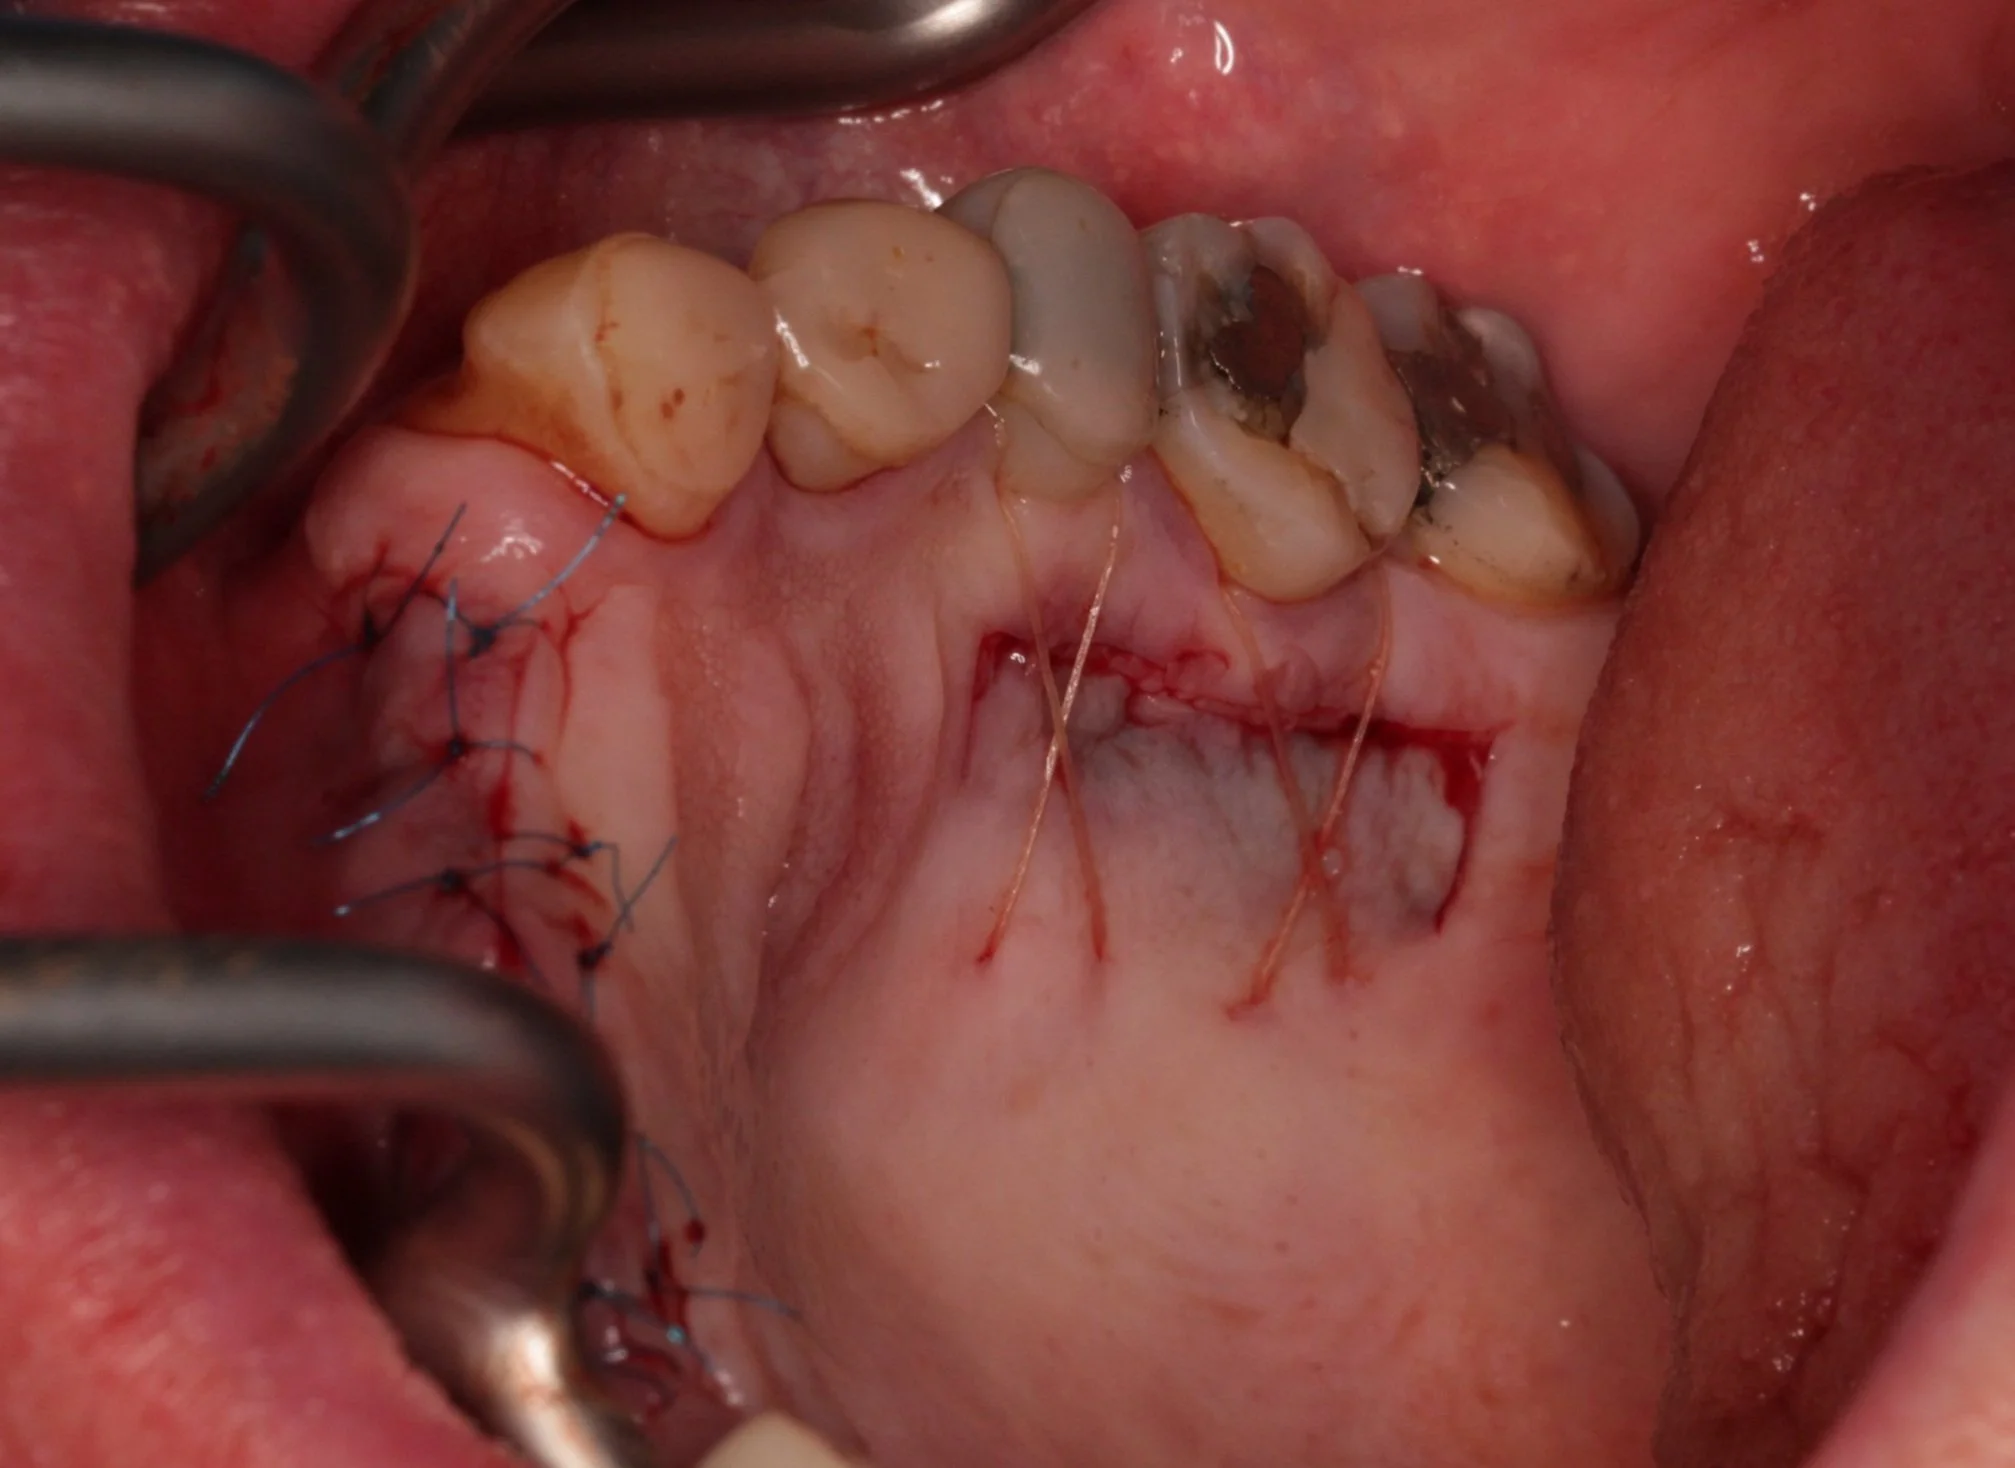

Extensive grafting procedures

Soft Tissue Grafting

Improving implant longevity